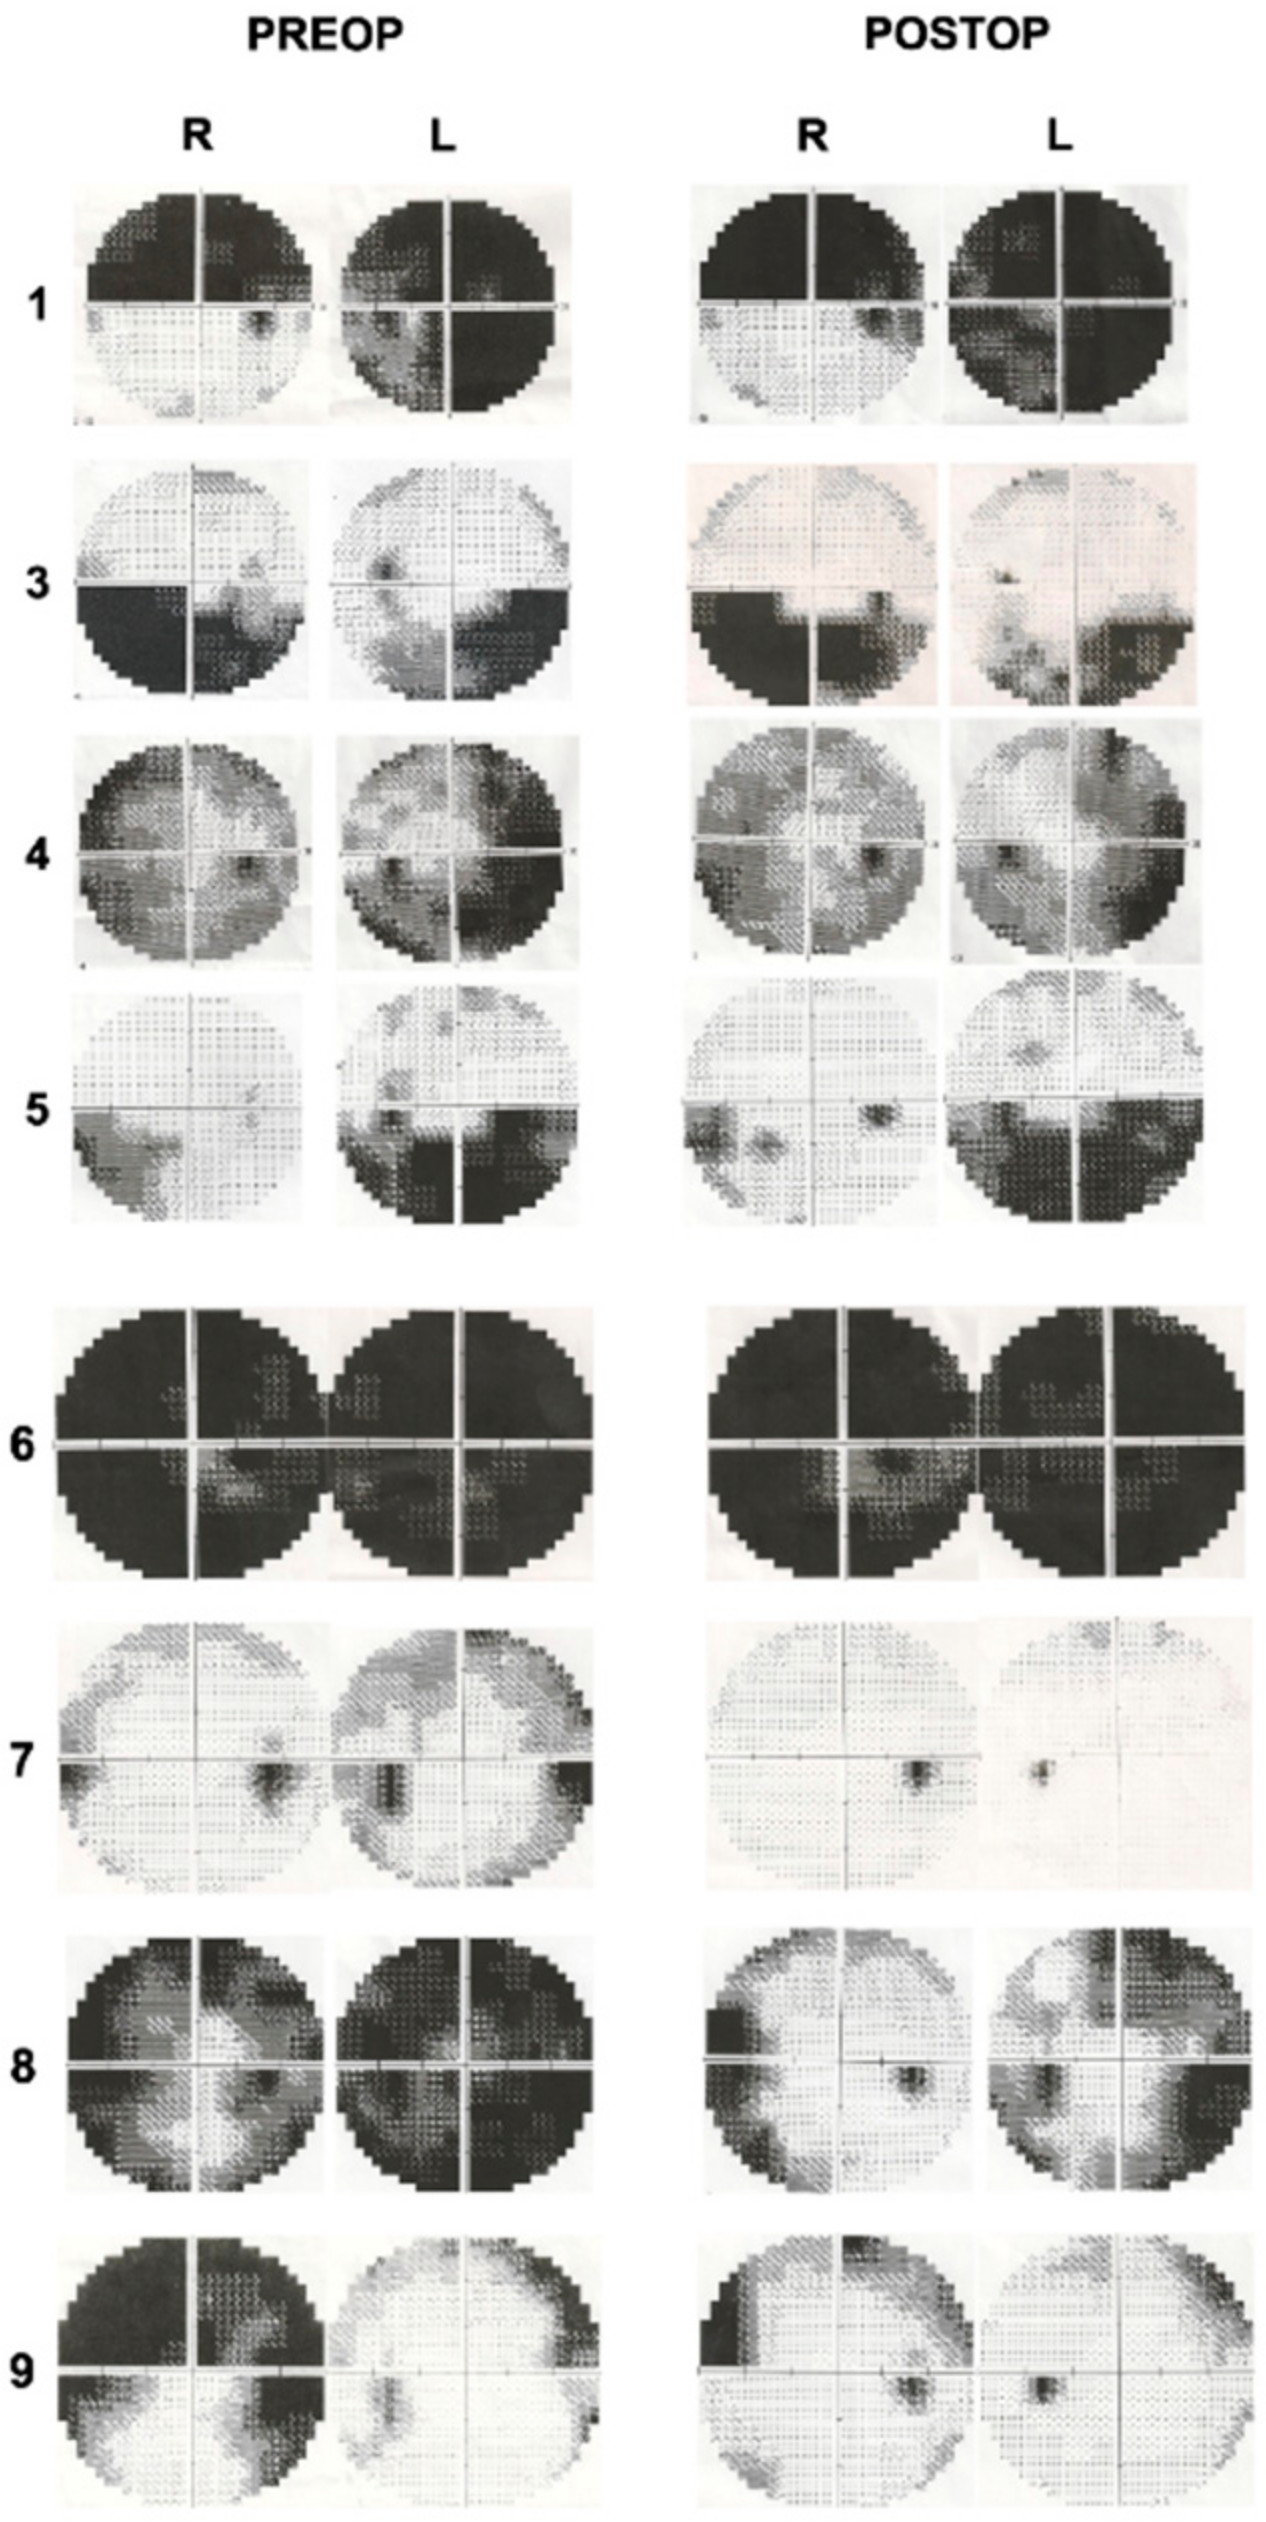

There were 9 patients (7 females and 2 males) between the ages of 21 and 72 included in this study, and the mean age was 40.8. MR venography examinations were normal in all patients. Two patients were pregnant (Cases 6 and 7). All patients had an impairment in visual acuity and/or visual field. There were also signs of papilledema and/or optic atrophy with subretinal fluid, retinal edema, and hemorrhages on the optic disc to different degrees in all patients. Headaches were observed in 6 out of 9 patients as another presenting symptom. Table 1 demonstrates the demographic and preoperative clinical features of all patients. An LP shunt procedure was performed in one patient (Case 2) at another center, a partial improvement was achieved, but visual impairment was persistent. In this case, despite the severe visual findings and bilateral optic atrophy, surgery was planned according to the visual evoked potential (VEP) test. Postoperatively, a little improvement in visual acuity was achieved, and the color vision has started on the left eye, but the VEP response was stable. The patients were followed up with for 9–48 months. Improvements in visual acuity were observed in 7 out of 9 patients (78%). Visual field defects improved in 5 out of 8 patients (62.5%). The preoperative and postoperative visual field examinations are demonstrated in Figure 3. Papilledema was resolved in all patients (100%). Headaches improved in all symptomatic patients (100%). Table 2 illustrates the postoperative clinical features of the patients. The preoperative and postoperative visual findings are demonstrated in three illustrative cases (Cases 7–9) in Figure 4, Figure 5 and Figure 6, respectively. No intraoperative or postoperative complications, such as a CSF leak, meningitis, and so on, were observed.

Figure 3.

Preoperative and postoperative visual field examinations of patients.